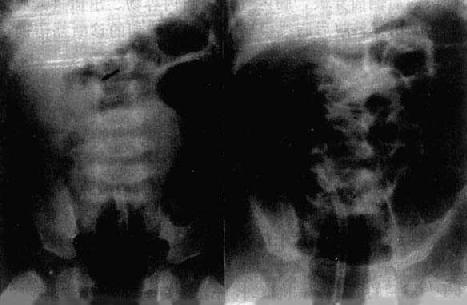

胃肠穿孔后,胃肠内容物,包括食物及消化液进入腹腔引起化学性和细菌性腹膜炎,胃肠液及炎性渗液不仅产生腹液征象,同时也可使相邻的胁腹脂线变模糊,使相邻的肠曲产生反应性淤积,甚至肠麻痹。 原发性腹膜炎的X线表现与胃肠穿孔所致全腹膜炎的表现相同,但无气腹征象。 从发病到出现X线征象,需要一定时间。除游离气腹征象出现较早外,其他征象的显示一般需6小时以上。因此,诊断时应考虑这一因素。 局限性腹膜炎可形成腹腔脓肿。腹腔脓肿多位于腹腔的间隙或隐窝中。常以腹壁、器官及韧带作为脓腔壁。主要X线表现是:①脓腔内有气体时,可见含气、液的空腔或气泡征象;②脓腔内无气体时,表现为软组织块影。如与实质器官相邻,则因缺乏对比而不易显示;③脓肿相邻器官受压移位;④脓肿周围炎症浸润,使相邻脂线增宽、密度增高,甚至消失;⑤如炎症扩散,则有关的间隙、隐窝因引流而有新脓肿形成;⑥上腹腔炎性淋巴引流,可出现胸腔积液、肺底炎症及小叶性肺不张等。 依脓肿所在部位,还可有一定的特别表现。例如,隔下脓肿,脓腔壁为腹壁、肝、隔及韧带,脓肿总是位于上腹腔的解剖间隙内,并位于上腹腔的周围。结肠下区脓肿,位于结肠旁沟时,结肠旁沟增宽,相邻结肠受压、移位,胁腹脂线也有一定改变。盆腔脓肿常使相邻盆壁脂线发生改变,直肠受压移向对侧。 (二)肠梗阻 肠梗阻(intestinal obstruction)一般分为机械性、动力性和血运性三类,以相械性肠梗阻最为常见。 机械性肠梗阻分为单纯性和绞窄性肠梗阻两种,前者只有肠道通畅障碍,而无血循环障碍,后者同时伴有血循环障碍,动力性肠梗阻分为麻痹性肠梗阻与痉挛性肠梗阻,肠道本身并无器质性病变。血运性肠梗阻见于肠系膜血栓形成或栓塞,有血循环障碍和肠肌运动功能失调。 X线检查的主要目的是;明确肠阻的类型。是机械性的还是动力性的,如果是动力性的,则应确定是痉挛性的还是麻痹性的,如果是机械性的,则应确定是单纯性的还是绞窄性的;是完全性的还是不完全性的;以及梗阻的位置和原因等。 不同类型肠梗阻的X线表现及诊断: 1.单纯性小肠梗阻 梗阻发生后3~6小时可出现X线表现。梗阻近端肠曲胀气扩大。立位像可见肠内高低不等液面,胀气肠曲呈弓形,多发的液面呈梯状排列。早期蠕动亢进,透视可见肠内液面上、下变化活跃。病情发展,肠曲胀气扩大逐渐加重,肠壁张力减低,蠕动明显减弱,液面增宽。肠壁和肠和肠粘膜皱襞除非是慢性梗阻,一般无明显增厚。梗阻远侧肠曲无气或仅见少许气体,因而可根据胀气扩大肠曲所涉及的范围来估计肠梗阻的位置(图4-1-4)。

图4-1-4 小肠梗阻(立位) 不同病因所致单纯性机械性肠梗阻还有一定的X线表现特点。例如,蛔虫团堵塞所致肠梗阻,小肠内的大量蛔虫,常扭曲成团、束。胆石性肠梗阻除有肠梗阻征象外,可发现腹内较大阳性结石,由于有胆肠内瘘,还可见肝内胆管积气征象。 2.绞窄性小肠梗阻 常见病因有:扭转、内疝、套叠和粘连等。由于有小肠系膜受累,肠曲活动被牵制。伸展受限,因而有肠曲向某一固定部位聚集的表现。肠壁循环障碍而导致肠壁增厚,粘膜皱襞增粗,肠内积液、液面较高等改变。闭袢性肠梗阻,还可见“假肿瘤”征。绞窄性小肠梗阻后期,可合并腹腔积液,由于合并动力性因素,结肠和直肠可以充气。 不同病因所致绞窄性肠梗阻还具有一定的X线表现特点。例如,小肠系膜扭转、内疝及粘连性肠梗阻合并肠段扭转时,常合并“假肿瘤”征;粘连性肠梗阻在不同体位的X线照片上,如仰卧前后位和侧卧水平位,可见充气积液的小肠曲活动减低,部分病例可出现肠曲纠集征象和肠曲转角较急的表现;急性肠套叠以回肠(或同时合并盲肠)套入结肠这一类型最为常见。腹部平片主要表现为低位小肠梗阻,有时右腹或上腹部可见肠形肿块及套叠远端结肠和套鞘积气征。钡剂、空气灌肠可见包括套入部梗阻端所形成的杯口状或圆形充盈缺损和套鞘因钡剂或气体进入两层肠壁之间所形成的弹簧状影(图4-1-5)。